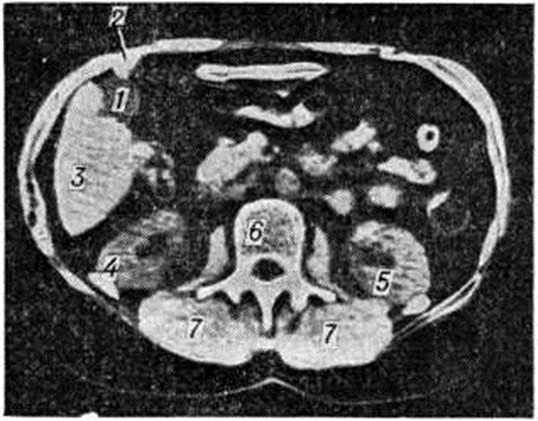

При пальпации живота отмечается болезненность в точке проекции желчного пузыря на переднюю брюшную стенку либо правее или левее, так как примерно в 20% случаев желчный пузырь располагается атипично. Выявляются положительные симптомы Кера (усиление болезненности при пальпации во время вдоха), Мерфи (больной не может глубоко вздохнуть из-за боли, возникающей при погружении пальцев исследующего в правое подреберье ниже края печени), Ортнера (боль при лёгком поколачивании по правой рёберной дуге ребром ладони), френикус-симптом (болезненность при надавливании в области прикрепления к ключице грудино-ключично-сосцевидной мышцы справа), Боаса — Свирского (болезненность при надавливании на остистые отростки IX — XII грудных позвонков или при поколачивании ребром кисти в этой области). Отмечается напряжённость мышц при пальпации живота в области правого подреберья. При развитии водянки или эмпиемы (смотри полный свод знаний: Желчный пузырь) наблюдается значительное увеличение желчного пузыря; дно его довольно отчётливо выступает из-под края печени, доступно для пальпации. При деструктивном, ферментативном холецистите и перфорации желчного пузыря появляются симптомы раздражения брюшины. В крови часто отмечается умеренный или выраженный лейкоцитоз, сдвиг лейкоцитарной формулы влево, ускоренная РОЭ. Из инструментальных методов исследования при остром холецистите применяют ультразвуковое исследование желчного пузыря, печени и поджелудочной железы (смотри полный свод знаний: Ультразвуковая диагностика), позволяющее выявить отёк, деформацию желчного пузыря, наличие конкрементов (рисунок 1), определить состояние протоков, печени и поджелудочной железы, и компьютерную томографию (смотри полный свод знаний: Томография компьютерная). Использование рентгенологическое методов исследования (холецистография, холангиография, ретроградная холангиография) и дуоденального зондирования при остром холецистите противопоказано. Дифференциальный диагноз при остром холецистите следует проводить с аппендицитом (смотри полный свод знаний), учитывая, что возможно атипичное расположение червеобразного отростка (выше подвздошной кости), с прободной язвой двенадцатиперстной кишки (смотри полный свод знаний: Язвенная болезнь), правосторонней пневмонией (смотри полный свод знаний) и плевритом (смотри полный свод знаний), поддиафрагмальным абсцессом (смотри полный свод знаний), внутрипечёночным абсцессом (смотри полный свод знаний: Печень), а также с инфарктом миокарда (смотри полный свод знаний). Об инфаркте миокарда всегда следует помнить ещё и потому, что он часто сочетается с заболеваниями желчных путей. Дифференциальная диагностика строится с учётом анамнеза и данных тщательного обследования больного. Так, при остром аппендиците боли возникают в эпигастральной области, но в последующем, как правило, локализуются и концентрируются в правой половине живота, не имеют характерной для холецистита иррадиации в область правой лопатки и надключичную область; отмечается усиление болезненности в правой половине живота при пальпации левой подвздошной области (симптом Ровсинга). О прободной язве двенадцатиперстной кишки свидетельствует отягощённый анамнез, отсутствие при перкуссии печёночной тупости, а также выявление на обзорной рентгенограмме брюшной полости газа под правым куполом диафрагмы в вертикальном положении больного. Для пневмонии и плеврита характерны кашель, боль в грудной клетке, связанная, как правило, с кашлем и дыхательными движениями. При постановке диагноза учитывают данные перкуссии, аускультации, а также результаты рентгенологическое исследования грудной клетки. Дифференциальная диагностика холецистита с поддиафрагмальным и внутрипечёночным абсцессами основывается на данных рентгенологическое исследования грудной клетки, а также ультразвукового исследования. Инфаркт миокарда диагностируется на основании данных электрокардиографического исследования. В сомнительных случаях приходится прибегать к лапароскопии (смотри полный свод знаний: Перитонеоскопия). Лечение. Больные с острым холециститом должны быть госпитализированы в хирургическое отделение. При деструктивных формах воспалительного процесса (флегмонозной, гангренозной), а также при развитии перитонита показано экстренное оперативное вмешательство. При относительно лёгком течении острого холецистита (катаральная форма) вначале проводят консервативное лечение. Больным назначают постельный режим, в течение 1—2 дней — голод, затем дробное (4—6 раз в день) питание, щадящую диету (отварные мясо и рыба, варёные овощи, паровой белковый омлет, творог, каша, отвары шиповника, чёрной смородины, фруктовые соки, печёные яблоки), антибиотики широкого спектра действия или (при их непереносимости либо нечувствительности к ним возбудителя) — сульфаниламиды, спазмолитические, седативные средства, при выраженном болевом синдроме — паранефральную новокаиновую блокаду (смотри полный свод знаний) или внутрикожное введение новокаина в болевую зону. В случае неэффективности консервативного лечения и отсутствия улучшения в состоянии больного через 24—72 часа после поступления в стационар производят срочную операцию. В. И. Стручков и А. В. Григорян (1976) отмечают, что по экстренным и срочным показаниям приходится оперировать около 26% больных, поступивших в хирургическое отделение по поводу острого холецистита. При решении вопроса об операции в острой стадии заболевания наличие или отсутствие камней в желчном пузыре, а также число предшествующих приступов во внимание не принимаются. Необходимость срочной операции диктуется степенью и распространённостью воспалительного процесса и наличием препятствия для оттока желчи. Длительная выжидательная тактика при остром холецистите не может считаться оправданной, поскольку часто воспалительный процесс прогрессирует, что нередко сопровождается деструктивными изменениями, образованием подпечёночного абсцесса (смотри полный свод знаний: Печень, патология) и других гнойных осложнений, усложняющих операцию, утяжеляющих послеоперационный период и увеличивающих число летальных исходов в послеоперационном периоде. Оперативному вмешательству предшествует интенсивная подготовка больного (смотри полный свод знаний: Предоперационный период), включающая проведение дезинтоксикационной и антибактериальной терапии, назначение антиспастических средств, коррекцию водно-электролитного баланса, профилактику холемического кровотечения и другие (смотри полный свод знаний: Желчные протоки; Желчный пузырь, операции). Оптимальным методом обезболивания является эндотрахеальный наркоз (смотри полный свод знаний: Ингаляционный наркоз) с применением мышечных релаксантов короткого действия. Разрез производят параллельно правой рёберной дуге (подрёберный), в диагностически неясных случаях используют срединный или параректальный доступы (смотри полный свод знаний: Лапаротомия). Чаще при холецистите производят холецистэктомию (смотри полный свод знаний), одним из обязательных условий которой является комплексное исследование желчных протоков во время операции, включая холангиографию (смотри полный свод знаний), а при необходимости и инструментальные методы — трансиллюминацию (смотри полный свод знаний), зондирование протоков (смотри полный свод знаний: Желчные протоки), холедохоскопию (смотри полный свод знаний) и другие Органосохраняющие операции — холецистостомия (смотри полный свод знаний), холецистолитотомия (смотри полный свод знаний: Холецистотомия), холецистохоледохостомия при холецистите, особенно калькулёзном, патогенетически не обоснованы, поскольку не устраняют причины заболевания. Однако при крайне тяжёлом состоянии больного или при невозможности выполнить холецистэктомию приходится прибегать к холецистостомии или холецистолитотомии, несмотря на то, что после этих операций, как правило, выздоровления не наступает и по ликвидации острых явлений приходится прибегать к повторному оперативному вмешательству. При холецистите, осложнённом холедохолитиазом, стриктурой фатерова соска, холангитом, перихоледохеальным лимфаденитом, желчным свищом и другие, наряду с удалением желчного пузыря во время операции устраняют препятствие оттоку желчи или производят коррекцию нарушений внепеченочных желчных протоков. С этой целью по показаниям производят холедохолитотомию (смотри полный свод знаний: Холедохотомия) с ушиванием наглухо отверстия в протоке или дренированием (смотри полный свод знаний) последнего с помощью Т-образной трубки либо через культю пузырного протока, а также холедоходуоденостомию (смотри полный свод знаний) или энтеростомию (наложение анастомоза между общим желчным протоком и тощей кишкой) с выключением сегмента тощей кишки по Ру или Брауну, трансдуоденальную папиллотомию, папиллосфинктеротомию или папиллосфинктеропластику (смотри полный свод знаний: Двенадцатиперстная кишка, Фатеров сосок). Рассечение стенозированного участка фатерова соска может быть осуществлено эндоскопически с помощью специального фибродуоденоскопа, что особенно показано больным пожилого и старческого возраста, состояние которых может быть отягощено сопутствующими заболеваниями сердечно-сосудистой системы, лёгких и других органов. У таких больных полостная операция (трансдуоденальная папиллосфинктеротомия) связана с большим риском. Осложнения, встречающиеся при холецистэктомии, в большинстве случаев возникают при ошибочной перевязке вместо пузырного протока и артерии других протоков или сосудов либо элементов печёночно-дуоденальной связки, а также при повреждениях или пересечении печёночного или общего желчного протока, печёночной артерии, воротной вены. Повреждения их во время операции обычно связаны с аномалиями развития желчных путей и сосудов данной области; они крайне опасны, так как могут явиться причиной желчного перитонита, обтурационной желтухи, некроза печени и поэтому требуют неотложного оперативного вмешательства. К хирургическим ошибкам относятся также не выявленные во время операции холедохолитиаз, стриктуры фатерова соска, неполное удаление желчного пузыря, длинная культя пузырного протока с оставшимися в ней конкрементами. После операции по поводу холецистита больного следует помещать в отделение реанимации или палату интенсивной терапии. Основными задачами раннего послеоперационного периода являются: полное выведение из наркоза, поддержание сердечной деятельности и кровообращения, функции внешнего дыхания, коррекция нарушения электролитного баланса и другие (смотри полный свод знаний: Послеоперационный период). При благоприятном течении послеоперационного периода на 2— 3-и сутки больного переводят в общую палату, разрешают вставать и ходить; контрольный дренаж при отсутствии отделяемого удаляют из брюшной полости на 2—3-и сутки, швы снимают на 7-е сутки, больных выписывают из стационара на 9— 10-й день. При осложнённом холецистите (холедохолитиаз, холангит, стриктуры желчных протоков и другие) либо осложнениях, возникающих во время или после операции, проводят соответствующее лечение. Послеоперационная летальность при неосложнённом холецистите, по данным Б. В. Петровского и О. Б. Милонова (1982), составляет 0,5%, а при осложнённом — 1,7%. Больные пожилого и старческого возраста, составляющие, по данным В. С. Маята и сотрудники (1976), половину всех больных с острым холециститом, должны привлекать повышенное внимание врачей. У этого контингента больных значительно чаще встречаются деструктивные формы холецистита, протекающие нередко без выраженных клинические, проявлений, а также осложнения (холедохолитиаз, холангит, внутренние желчные свищи, механическая желтуха, гепатит, панкреатит и другие) часто обусловленные длительным (на протяжении многих лет) течением заболевания. Большинство больных пожилого и старческого возраста страдают, кроме того, серьёзными сопутствующими заболеваниями сердечно-сосудистой системы и лёгких, сахарным диабетом и другие, что значительно отягощает течение острого холецистита и увеличивает риск оперативного вмешательства. Послеоперационная летальность среди лиц пожилого и старческого возраста в 8—10 раз выше, чем у остальных больных. Поэтому перед экстренной и срочной операцией больным пожилого и старческого возраста необходима особенно тщательная предоперационная подготовка, включающая ликвидацию интоксикации, коррекцию водно-солевого баланса, а также мероприятия, направленные на нормализацию сердечно -сосудистой деятельности, предупреждение тромбоэмболических осложнений, печёночно-почечной недостаточности, нарушений внешнего дыхания и лечение сопутствующих заболеваний. В связи с повышенным риском операции на высоте приступа у больных пожилого и старческого возраста с сопутствующими заболеваниями в отдельных случаях может быть предпринята транспариетальная декомпрессионная пункция желчного пузыря, осуществляемая через ткань печени или сальник под контролем лапароскопа (смотри полный свод знаний: Перитонеоскопия). При этом удаляют жидкое инфицированное содержимое желчного пузыря и в его полость вводят смесь, состоящую из антибиотиков широкого спектра действия и кортикостероидов, что приводит к быстрому стиханию острого воспаления. В некоторых случаях в полости желчного пузыря временно оставляют тонкий дренаж (микрохолецистостомия). Одновременно выполняют лапароскопическую холецистохолангиографию (смотри полный свод знаний: Холангиография), позволяющую провести наиболее информативное исследование желчных путей, крайне важное для определения показаний к последующему оперативному вмешательству. При холедохолитиазе (особенно при наличии вколоченного камня фатерова соска), осложнённом обтурационной желтухой, методом выбора у больных пожилого и старческого возраста, находящихся в тяжёлом состоянии, является эндоскопическая папиллотомия, способствующая декомпрессии желчевыводящих путей и освобождению общего желчного протока от камней. Иногда с целью декомпрессии проводят эндоскопическое назобилиарное дренирование (в общий желчный проток через фатеров сосок с помощью эндофиброскопа вводят тонкий зонд, который затем перемещают из полости рта в полость носа). В случае быстрого стихания острого процесса на фоне консервативной терапии всем больным с острым холециститом следует произвести клинико-лабораторное и рентгенологическое исследование (холецистохолангиографию). При выявлении у больных калькулёзного холецистита их следует оперировать через 2—3 недель, не выписывая из стационара (ранняя плановая операция), либо в состоянии полной ремиссии, спустя 4—6 месяцев после приступа. Операция в холодном периоде заболевания предпочтительна, так как сопровождается меньшим числом осложнений во время операции и в послеоперационном периоде, а также более низкой (в 5—6 раз) летальностью по сравнению с экстренными и срочными операциями. Своевременно произведённая операция позволяет добиться полного выздоровления больных и избежать осложнений со стороны других органов желудочно-кишечные тракта. Прогноз острого холецистита зависит от формы заболевания и своевременности лечения. Так, при катаральном холецистите рано начатое лечение может привести к выздоровлению, однако чаще заболевание принимает хронический характер. При остром гнойном холецистите (флегмонозном, гангренозном) в случае отсутствия осложнений со стороны печени, поджелудочной железы и желчных протоков после своевременного оперативного вмешательства прогноз чаще благоприятный. Прогноз острого гнойного холецистита у больных с сопутствующими заболеваниями сердечно-сосудистой системы, хронический заболеваниями лёгких, почек и другие, у лиц пожилого возраста, а также при присоединении осложнений серьёзный. Профилактика сводится к правильному питанию и режиму, борьбе с адинамией, ожирением, запорами, заболеваниями органов брюшной полости. ХРОНИЧЕСКИЙ ХОЛЕЦИСТИТХронический холецистит может возникнуть самостоятельно или явиться исходом острого холецистита. Он бывает калькулёзным и некалькулёзным. Определение формы заболевания имеет большое практическое значение при выборе тактики лечения больного. Патологическая анатомия. Хронический холецистит может быть катаральным и гнойным. При хронический катаральном холецистите стенка желчного пузыря плотная, склерозированная, отмечается атрофия слизистой оболочки и гипертрофия мышечного слоя. Микроскопически под эпителием выявляются многочисленные макрофаги, содержащие холестерин, а также лимфоплазмоцитарные инфильтраты в склерозированной строме. При рецидиве заболевания наблюдается полнокровие сосудов, отёк стенки желчного пузыря и инфильтрация её полиморфно-ядерными лейкоцитами. В ряде случаев макроскопически выявляют утолщение и полиповидные изменения складок слизистой оболочки с диффузной инфильтрацией стенок липидами, создающие характерное сетчатое её строение. Микроскопически эпителий на отдельных участках отсутствует, на других — разрастается с образованием мелких полипов. В строме и подслизистом слое отмечается большое количество ксантомных клеток (смотри полный свод знаний: Ксантома). При хронический гнойном холецистите процесс охватывает все слои стенки желчного пузыря, что приводит к её склерозированию. В толще стенки из синусов Рокитанского—Ашоффа образуются псевдодивертикулы и абсцессы, являющиеся источниками повторных обострений процесса. Слизистая оболочка атрофична, утолщена, под ней среди тяжей фиброзной ткани и гипертрофированных мышечных волокон определяются воспалительные инфильтраты, на её поверхности появляются изъязвления. Язвы на слизистой оболочке заполняются грануляционной тканью, рубцуются и в последующем эпителизируются за счёт сохранившихся клеток ходов Лушки. Последние разрастаются, ветвятся, достигают субсерозного слоя; часть из них кистозно расширена, заполнена муцином. Среди грануляционной ткани встречаются аденоматозные структуры. Местами в толще стенки откладываются соли кальция, которые в редких случаях могут инкрустировать весь желчный пузырь. Постепенно происходит деформация желчного пузыря, образование спаек с соседними органами (перихолецистит). Серозная оболочка в местах, свободных от спаек, имеет вид глазури. В результате этих изменений желчный пузырь утрачивает свои функции, превращается в очаг хронический инфекции. В далеко зашедших случаях он представляет собой склерозированный деформированный мешок, заполненный конкрементами и гноем. Микроскопически в стенке желчного пузыря отмечаются выраженные склеротические изменения, а также участки лимфоплазмоцитарной инфильтрации с примесью макрофагов и эозинофильных лейкоцитов. Иногда встречаются лимфоидные фолликулы со светлыми центрами размножения. Макропрепараты желчного пузыря при хроническом калькулёзном холецистите — смотри цветной рисунок 11, 12, 13. Воспалительный процесс в желчном пузыре при хронический холецистите может сопровождаться различными осложнениями как со стороны самого желчного пузыря, так и со стороны окружающих органов. При перфорации стенки желчного пузыря развивается разлитой желчный перитонит. Обтурация пузырного протока камнем, реже аденоматозными разрастаниями при шеечном некалькулёзном холецистите может привести к водянке желчного пузыря, при которой пузырь напряжён и заполнен белой желчью. При активизации воспалительного процесса может развиться эмпиема желчного пузыря (в просвете его содержится желчь с гноем). Длительное нахождение конкрементов в просвете пузыря может вызвать пролежень его стенки и развитие внутреннего желчного свища (смотри полный свод знаний: Желчные свищи), при котором возникает сообщение желчного пузыря с другими полыми органами (поперечной ободочной кишкой, двенадцатиперстной кишкой, желудком). При обострении процесса возможно образование паравезикулярного подпечёночного, поддиафрагмального абсцессов, при прорыве абсцесса через переднюю брюшную стенку может образоваться наружный желчный свищ. В связи с тем, что желчный пузырь находится в анатомической и физиологической связи с печенью, желчными протоками и поджелудочной железой, изолированный хронический холецистит наблюдается редко. Воспалительный процесс может распространяться на желчные протоки с развитием холецистоангиохолита (ангиохолецистита), на печень с развитием реактивного гепатита, а в ряде случаев и билиарного цирроза печени. В поджелудочной железе могут возникнуть токсический отёк, очаговый некроз, хронический интерстициальный панкреатит с переходом в фиброз. Это обусловлено панкреатобилиарным рефлюксом (смотри полный свод знаний) в результате холестаза, а также лимфогенным распространением инфекции на ткань поджелудочной железы. При попадании инфицированной желчи в проток поджелудочной железы может развиться острый геморрагический некроз поджелудочной железы (при лимфогенном распространении инфекции воспалительный процесс в поджелудочной железе носит хронический характер). Редко развивается специфическое воспаление желчного пузыря. Туберкулёз желчного пузыря (смотри полный свод знаний: Туберкулёз внелёгочный) характеризуется появлением в его стенке милиарных бугорков и крупных узлов с очагами творожистого некроза, на месте которых в последующем образуются язвы. При третичном сифилисе (смотри полный свод знаний) в стенке желчного пузыря могут обнаруживаться гуммы. Клиническая картина. При хронический холецистите больной длительное время ощущает горечь во рту, умеренную болезненность или чувство тяжести в области правого подреберья. Интенсивность болей зависит от степени и длительности воспалительного процесса в желчном пузыре (наличие перихолецистита) и сопутствующей дискинезии. При сопутствующей дискинезии по гипотоническому типу (смотри полный свод знаний: Желчный пузырь, патология) боль незначительная, монотонная, постоянная; при сопутствующей дискинезии по гипертоническому типу — резкая, приступообразная, напоминающая желчную колику. При перихолецистите боль отличается постоянством и связана с изменением положения тела. Боли иррадиируют в правую поясничную область, правое плечо и лопатку, иногда отмечается иррадиация болей влево, в область сердца. Больные жалуются на диспептические расстройства (отрыжку, тошноту, рвоту). Температура может повышаться до субфебрильных, реже — до более высоких цифр. Хронический холецистит протекает с периодическими обострениями, сопровождающимися усилением описанных выше симптомов. Обострения чаще бывают вызваны погрешностями в диете, чрезмерной физической нагрузкой, острыми воспалительными заболеваниями других органов. Хронический холецистит чаще протекает доброкачественно. В зависимости от особенностей течения выделяют латентную и рецидивирующую формы заболевания. Диагноз устанавливают на основании анамнеза, клинические картины, данных лабораторного, рентгенологического и инструментального исследований. При осмотре выявляются те же симптомы, что и при остром холецистите (смотри полный свод знаний: выше Острый холецистит), но менее выраженные. В крови может быть незначительный лейкоцитоз, небольшое ускорение РОЭ, в ряде случаев отмечается нестойкая уробилинурия (смотри полный свод знаний). При вовлечении в процесс поджелудочной железы обнаруживают амилорею, креаторею (смотри полный свод знаний: Кал), стеаторею (смотри полный свод знаний). Достаточно информативным и широко доступным методом лабораторной диагностики при некалькулёзном хронический холецистите, который можно проводить как в стационаре, так и в условиях поликлиники, является исследование желчи путём хроматического фракционного дуоденального зондирования. Преимущество этого метода перед обычным (нехроматическим) дуоденальным зондированием (смотри полный свод знаний) заключается в окрашивании пузырной порции желчи (порции В) в синий цвет, что позволяет отличить эту порцию от других. Хроматическое фракционное дуоденальное зондирование позволяет точно установить время выделения и количество желчи в разных порциях; это даёт возможность более чётко диагностировать сопутствующую гипотоническую или гипертоническую дискинезию. Так, если в норме желчный пузырь обычно содержит 30—50 миллилитров желчи, то при хронический холецистите, сочетающемся с гипотонической дискинезией, в желчном пузыре скапливается до 150— 200 миллилитров желчи и более, причём выделяется она значительно медленнее, чем в норме. Хроматическое фракционное дуоденальное зондирование проводят по общепринятой методике, но предварительно за 12 часов до процедуры больной принимает внутрь 0,15—0,3 грамм метиленового синего в желатиновой или крахмальной капсуле. Часто даже при многократном зондировании порцию В желчи не получают, что может быть связано с облитерацией или сморщиванием желчного пузыря и является признаком хронический холецистита. Порцию В не удаётся получить также при перихолецистите в связи с нарушением сократительной способности желчного пузыря. Микроскопическое исследование желчи позволяет обнаруживать в ней скопление клеток цилиндрического эпителия, слизи, кристаллов билирубината кальция, холестерина, а иногда и паразитов. При бактериологические исследовании для посева следует брать желчь отдельно из разных порций. Чаще при хронический холецистите выявляют смешанную колибациллярную и кокковую микрофлору. По мере развития воспалительного процесса в желчи понижается содержание холевой кислоты, билирубина, липопротеинового комплекса, изменяется холатохолестериновый индекс.

Окончательный диагноз хронический холецистита устанавливают после проведения рентгенологическое и инструментального обследований. Важным методом исследования при хронический холецистите является рентгенологический. Начинать обследование следует с обзорной рентгенографии (смотри полный свод знаний) области правого подреберья, при которой можно обнаружить тени рентгеноконтрастных камней (рисунок 2) или обызвествление стенок желчного пузыря (рисунок 3). После этого производят холецистографию (смотри полный свод знаний) или сочетанную холецистохолангиографию, позволяющие установить наличие в желчном пузыре камней, что проявляется дефектом наполнения (рисунок 4), а также выявить деформацию желчного пузыря (рисунок 5) и нарушение его функции при некалькулёзном холецистите. С помощью ультразвукового исследования определяют состояние стенки пузыря, наличие в нем конкрементов, а также сократительную способность желчного пузыря. Все большее распространение получают метод радиоизотопного исследования желчного пузыря (смотри цветной рисунок 12 и 13), а также компьютерная томография печени, желчного пузыря (рисунок 6) и поджелудочной железы, которые применяются прежде всего у больных с желтухой и у лиц, которым противопоказано (например, в связи с аллергией) обычное рентгенологическое исследование. У больных с желтухой и (или) при непереносимости контрастного вещества (при его внутривенном введении) для уточнения диагноза можно произвести ретроградную холангиографию (смотри полный свод знаний) во время фибродуоденоскопии. Это даёт возможность получить прямое контрастирование желчного пузыря, позволяющее при некалькулёзном холецистите выявить его деформацию (рисунок 7) и нарушение оттока желчи, при калькулёзном холецистите — конкременты в просвете желчного пузыря, а иногда в общем желчном протоке. Дифференциальный диагноз. Хронический холецистит следует дифференцировать с язвенной болезнью, хронический воспалительными заболеваниями мочевыводящих путей и толстой кишки. Дифференциальную диагностику между хронический холециститом и язвенной болезнью проводят на основании особенностей болевого синдрома, сезонности обострений, данных рентгенологического и эндоскопического исследований (смотри полный свод знаний: Язвенная болезнь). При хронический заболеваниях мочевыводящих путей боли иррадиируют в паховую область, отмечаются дизурические явления, изменения в моче. Хронический воспалительные заболевания кишечника исключаются на основании данных рентгенологического и эндоскопического исследования (смотри полный свод знаний: Колит). Лечение. Хронический калькулёзный холецистит и осложнённые формы хронический некалькулёзного холецистита подлежат оперативному лечению (смотри полный свод знаний: Желчнокаменная болезнь, Холецистэктомия). Консервативно лечат неосложнённые формы некалькулёзного холецистита и обострения других форм хронический холецистита, когда больной категорически отказывается от оперативного лечения или проведение его невозможно из-за тяжёлых сопутствующих заболеваний. Консервативные мероприятия направлены на ликвидацию воспалительного процесса, борьбу с застоем желчи и дискинезией желчных путей. Больным назначают постельный или полупостельный режим, дробное питание, щадящую диету (смотри полный свод знаний: выше Острый холецистит), которую расширяют при улучшении самочувствия через 2 недель, противовоспалительные средства (антибиотики или сульфаниламиды) в течение 2—3 недель Применение желчегонных средств зависит от типа сопутствующей дискинезии. При дискинезии по гипотоническому типу показаны холецистокинетики — сульфат магния, карловарская соль, оливковое масло, гипофизин, сорбит, ксилит и другие При дискинезии по гипертоническому типу целесообразно применять холеретики (холагол, холосас), а а также спазмолитические средства (атропин, препараты белладонны, ношпа, платифиллин и другие). При затруднении в определении типа дискинезии, а также в случаях смешанных дискинезий рекомендуют желчегонные средства растительного происхождения (отвар кукурузных рылец, шиповника и другие), обладающие сочетанным (в большей степени холеретическим) умеренным эффектом. При сочетании холецистита с дискинезией по гипертоническому типу рекомендуют также седативные средства (препараты валерианы, пустырника, бром и другие). В случае вовлечения в патологический процесс поджелудочной железы в комплекс лечебный мероприятий включают ферментную терапию (смотри полный свод знаний: Панкреатит). При хронический некалькулёзном холецистите с упорным течением и наличием у больного аллергических реакций рекомендуются антигистаминные средства (димедрол, супрастин и другие), в случае иммунной недостаточности — левамизол. Эффективным при хронический холецистите является дуоденальное зондирование или беззондовый тюбаж (смотри полный свод знаний), а также водолечение. При дискинезии по гипотоническому типу назначают щелочные воды с высокой минерализацией (Ессентуки № 17, Арзни, Баталинская), при дискинезии по гипертоническому типу — подогретую минеральную воду с меньшей концентрацией солей и более низким содержанием газа (Ессентуки № 4, № 20, Славяновская, Смирновская, Железноводская). При назначении минеральной воды следует учитывать состояние секреторной функции желудка. Физиотерапевтические процедуры показаны при хронический холецистите вне обострения. Наиболее эффективны: диатермия (смотри полный свод знаний), индуктотермия (смотри полный свод знаний), УВЧ (смотри полный свод знаний: У ВЧ-терапия), ультразвук (смотри полный свод знаний: Ультразвуковая терапия), грязевые, озокеритовые или парафиновые аппликации на область желчного пузыря (смотри полный свод знаний: Грязелечение, Озокеритолечение, Парафинолечение), радоновые и сероводородные ванны (смотри полный свод знаний: Ванны, Радоновые воды, Сульфидные воды). В стадии ремиссии больным целесообразно назначать санитарно-курортный лечение на курортах Ессентуки, Боржоми, Железноводск, Трускавец, Моршин, Дорохово и другие Лечение хронический холецистита длительное. Больные должны находиться под диспансерным наблюдением. Для предупреждения обострений им назначают диету, щадящий режим труда, проводят санацию очагов хронический инфекции, а также 2—3 раза в год профилактическое противорецидивное лечение. Прогноз, как правило, благоприятный. Профилактика заключается в правильном питании и режиме, борьбе с адинамией, ожирением, заболеваниями органов брюшной полости, в своевременном и правильном лечении острого холецистита. Смотри полный свод знаний: Желчнокаменная болезнь.